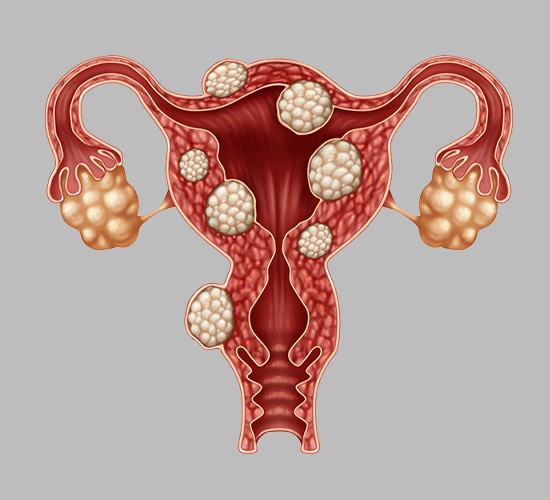

Uterine Fibroids Treatment

We offer advanced treatments for uterine fibroids, relieving symptoms and improving fertility through medication, minimally invasive procedures, or surgery.

Endometriosis Treatment

Specialized endometriosis treatments help manage pain, improve fertility, and restore reproductive health through medication, surgery, or hormonal therapy.